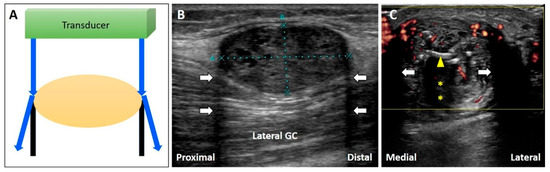

3.1. Posterior Enhancement

3.1.1. Physics

3.1.2. Clinical Examples